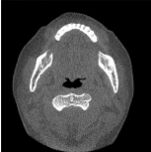

33.某人頭部創傷,到院前心跳停止(out-of-hospital cardiac arrest, OHCA),經心肺復甦術及氣管內管(endotracheal tube)插管治療後,接受電腦斷層檢查,下圖箭號處最適當的敘述為何? (A)食道插管(esophageal intubation) (B)氣管狹窄(tracheal stenosis) (C)食道破裂(esophageal perforation) (D)正常插管後現象(normal postintubation phenomenon)